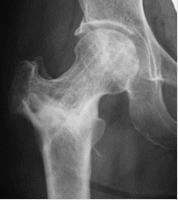

大腿骨頭壊死に対する骨温存手術として、大腿骨骨切術、減圧骨移植術を、年齢や骨壊死範囲、社会的状況を考慮して行っております。いずれの手術でも、術後6週間後から部分荷重を開始し、退院は2ヶ月程度で可能となります。

48歳、大腿骨頭前方回転骨切術後半年

術後3年